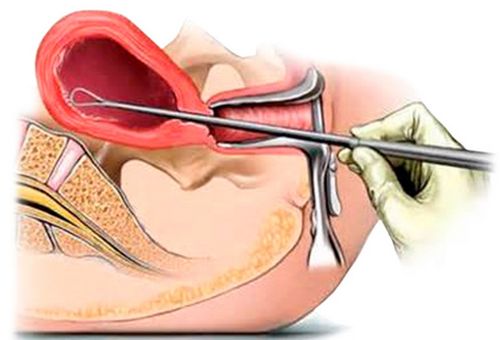

При підозрі на завмерла вагітність жінку необхідно терміново госпіталізувати.Після виконання обстеження (ХГЧ, УЗД на ранніх термінах і АПФ у 2 триместрі, коагулограма) проводять дбайливу евакуацію ембріона.

Можливий варіант з вичікувальною тактикою, коли зародок мертвий менш ніж 2 тижні (якщо це сталося на ранньому терміні вагітності) і немає ознак почався аборту і інфікування матки. У таких випадках рівень ХГЧ в організмі жінки стрімко падає, з'являються скорочення матки, плодове яйце виштовхується. Однак найчастіше вдаються до використання хірургічного методу, а саме оболонки з плодовим яйцем вискоблюється або піддаються вакуумної аспірації.Можливо також застосування медикаментозного аборту (на терміни до 7 тижнів) шляхом призначення блокатора прогестерону «мифегин».

Після хірургічного або іншого звільнення порожнини матки від зародка в обов'язковому порядку виконують гістероскопію. В післяопераційному періоді потрібно прийом антибіотиків для профілактики розвитку хоріанамніоніта і ендометриту.

У разі загибелі плоду після 14-16 тижні його евакуацію виконують шляхом транцервікального введення (амніоцентезу) гіпертонічного розчину натрій хлориду або простагландинів, або ж внутрішньовенним введенням розчину простагландинів.